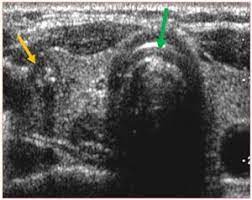

But, can this imaging test actually detect cancer? Neck lumps are a common presentation in the general population, presenting in both children and adults, and have a wide range of potential differential diagnoses. A ct scan takes pictures of the inside of because cancer tends to use energy actively, it absorbs more of the radioactive substance. These sound waves are not detectable by human hearing. Lung cancer tend to be found in the lungs. Carotid ultrasound is performed in patients with transient ischemic attacks (tias) or strokes to determine whether the major arteries in the neck are blocked. Ultrasound is sound waves with frequencies higher than the upper audible limit of human hearing. Sometimes the cancer cells can spread into the nearby lymph nodes.

An ultrasound of the neck uses high frequency sound waves to create a live image from inside of a patient's body. These sound waves are not detectable by human hearing. Sometimes the cancer cells can spread into the nearby lymph nodes. It can detect abnormal tissues, growths, and cysts and give a suspicion of. An ultrasound uses sound waves to create a picture of internal organs. What an ultrasound can detect? Computed tomography (ct or cat) scan. Similarly, being able to identify precancerous tissue abnormalities accurately. Ultrasound may be used to guide a needle into pockets of fluid accumulated in the body that need to be drained (for example, an abscess, pleural effusions, or ascites). An mri produces sharp, detailed images that can help detect cancerous cells in the head and neck. Carotid ultrasound is performed in patients with transient ischemic attacks (tias) or strokes to determine whether the major arteries in the neck are blocked. Diagnostic imaging for head and neck cancer. But the results are dependent on the experience of the sonographer(radiologist).

An ultrasound may be used to check for certain cancers in various different ways. What an ultrasound can detect? 31 533 просмотра • 28 сент. Cysts or abnormal growths in the liver, spleen, or pancreas. Brook's personal experiences as a patient with throat they are also used to detect cancer and follow up its progression and response to therapy. Some genetic disorders, such as fanconi anemia, can increase the risk of developing precancerous lesions and cancers early in life (30). Sometimes the cancer cells can spread into the nearby lymph nodes. Ultrasound can detect abnormalities indicating cancer in breast, liver, etc., but a definite diagnosis requires further tests like ct or mri scan. However, ultrasound does not produce images with the same level of clarity or detail as a ct or mri scan, nor can it confirm a cancer diagnosis on its own. A scanner then detects this substance to produce images. Ultrasound image of a neck mass. For head and neck cancers, immunotherapy medications may act on a specific protein in immune. An ultrasound of the neck uses high frequency sound waves to create a live image from inside of a patient's body.